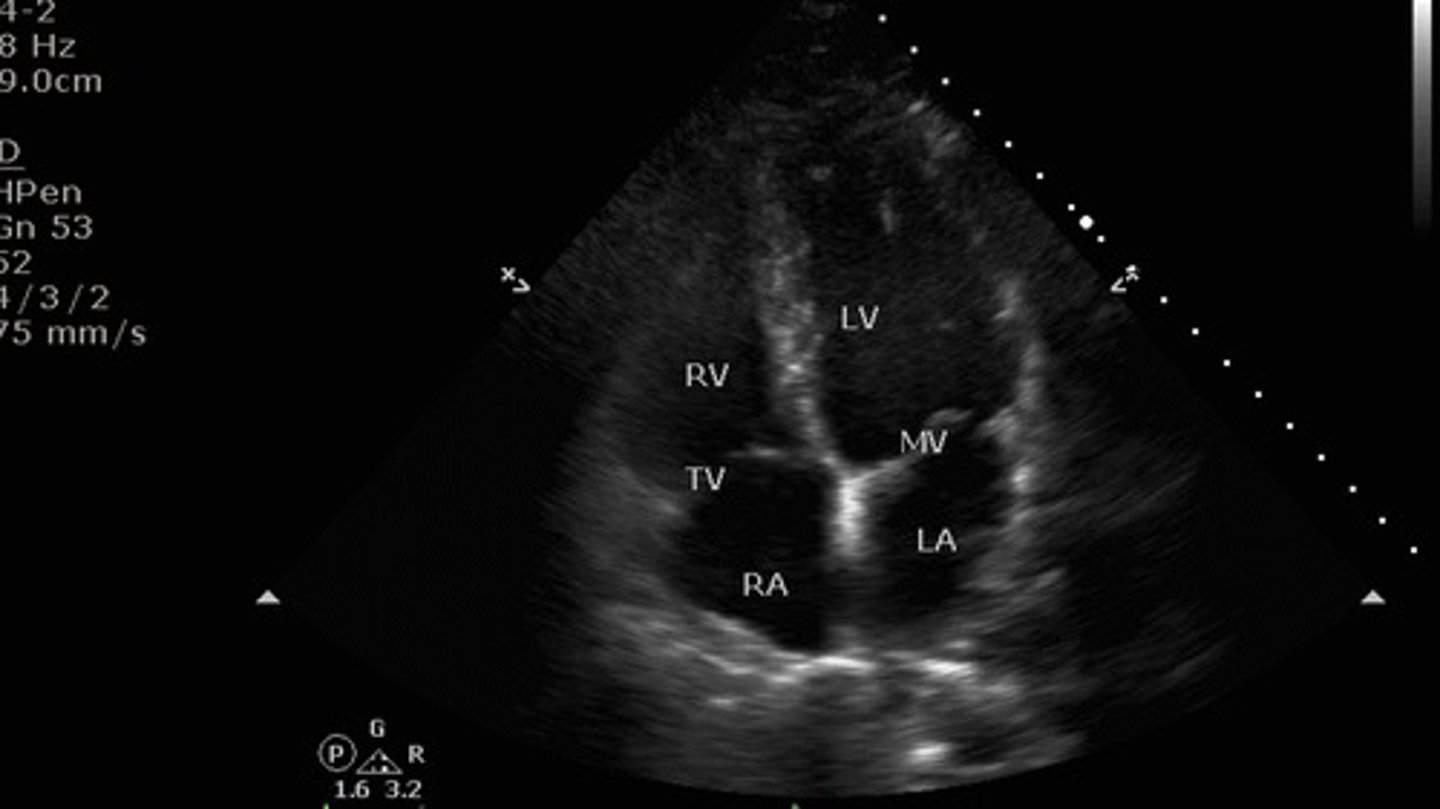

Apical 4 chamber view

what view is this?

toward the bed with patient supine

where is the indicator mark pointed for the 4 chamber view?

1. right ventricle

2. tricuspid valve

3. right atrium

4. left ventricle

5. mitral valve

6. left atrium

identify the numbered structures